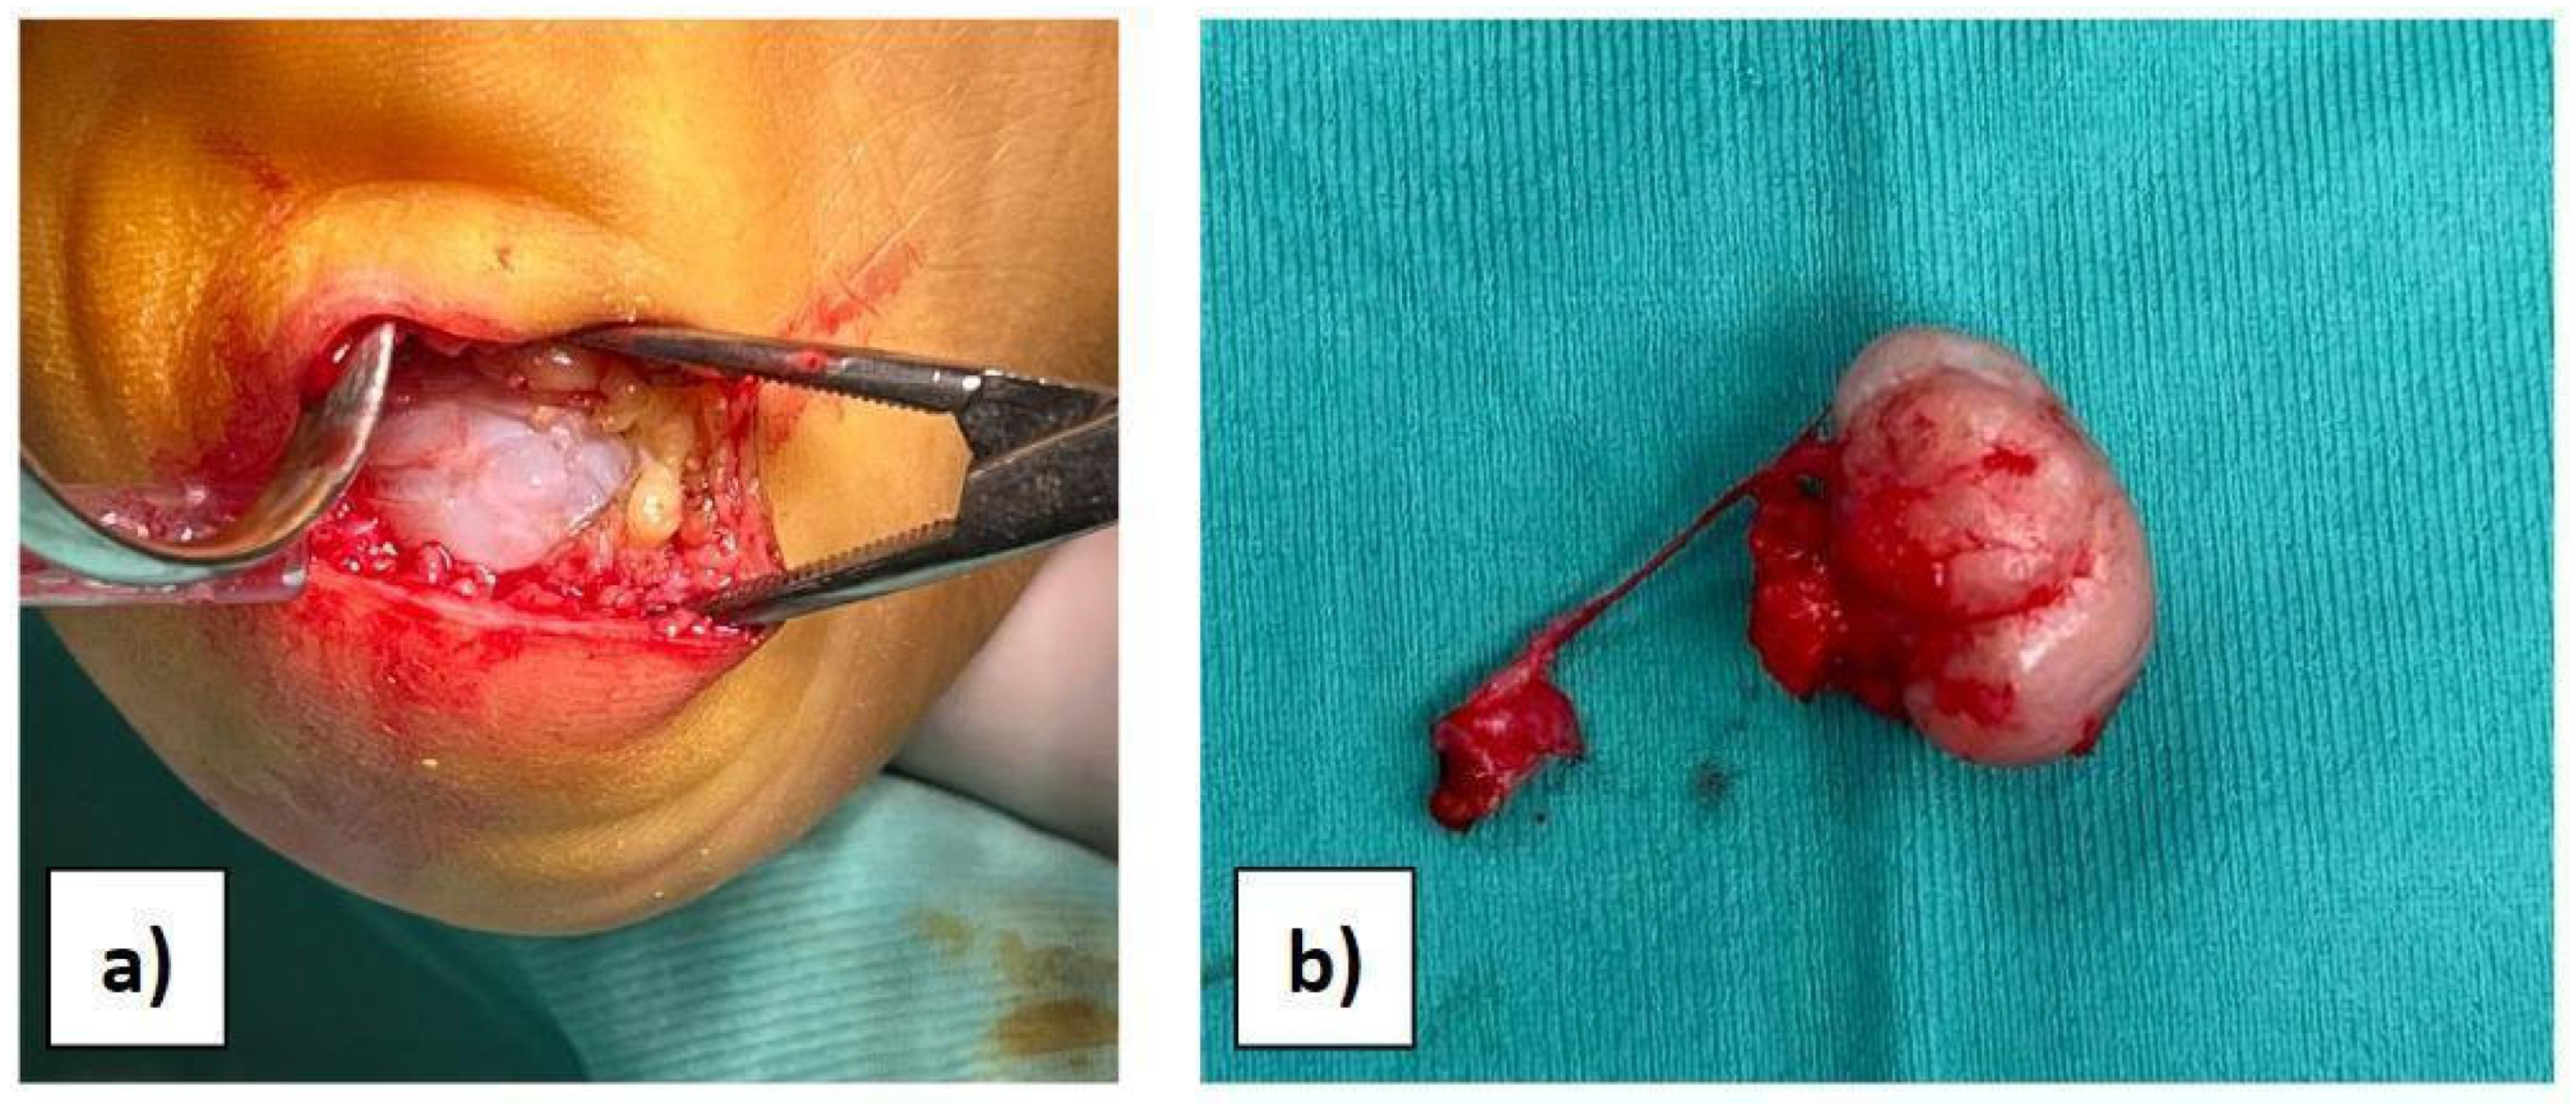

2. Clinical Case